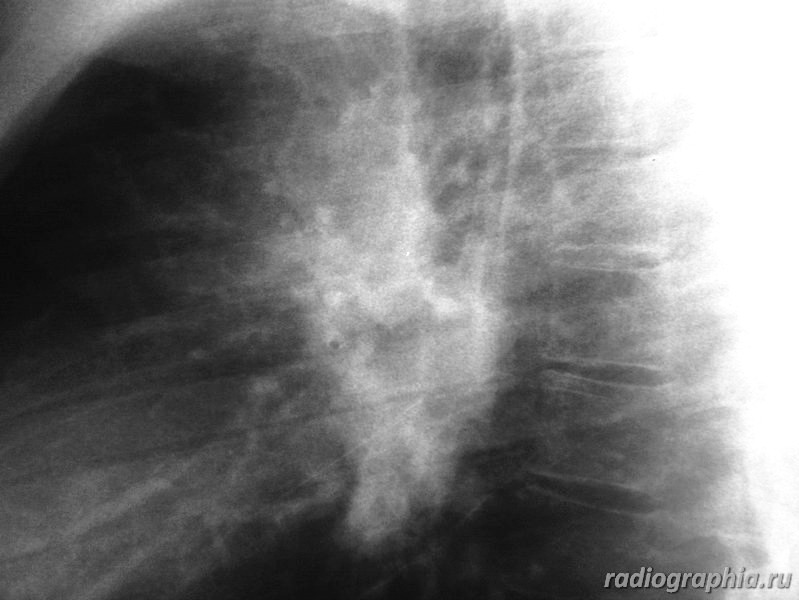

Рентгенография ОГК. Женщина средних лет.

интересует предыдущая рентгенодокументация (если есть :lol: ), анамнез заболевания. На момент осмотра больше данных за расширение легочных артерий , возможно начальные рентгенпризнаки развивающегося идиопатического легочного фиброза.Саркоидоз со стопроцентной уверенностью тоже исключать не стала бы.

Расширение верхнего средостения, широкие корни. У пациентки диагностирована лимфома. Была выполнена медиастиноскопия с забором лимфатических узлов на морфологию.